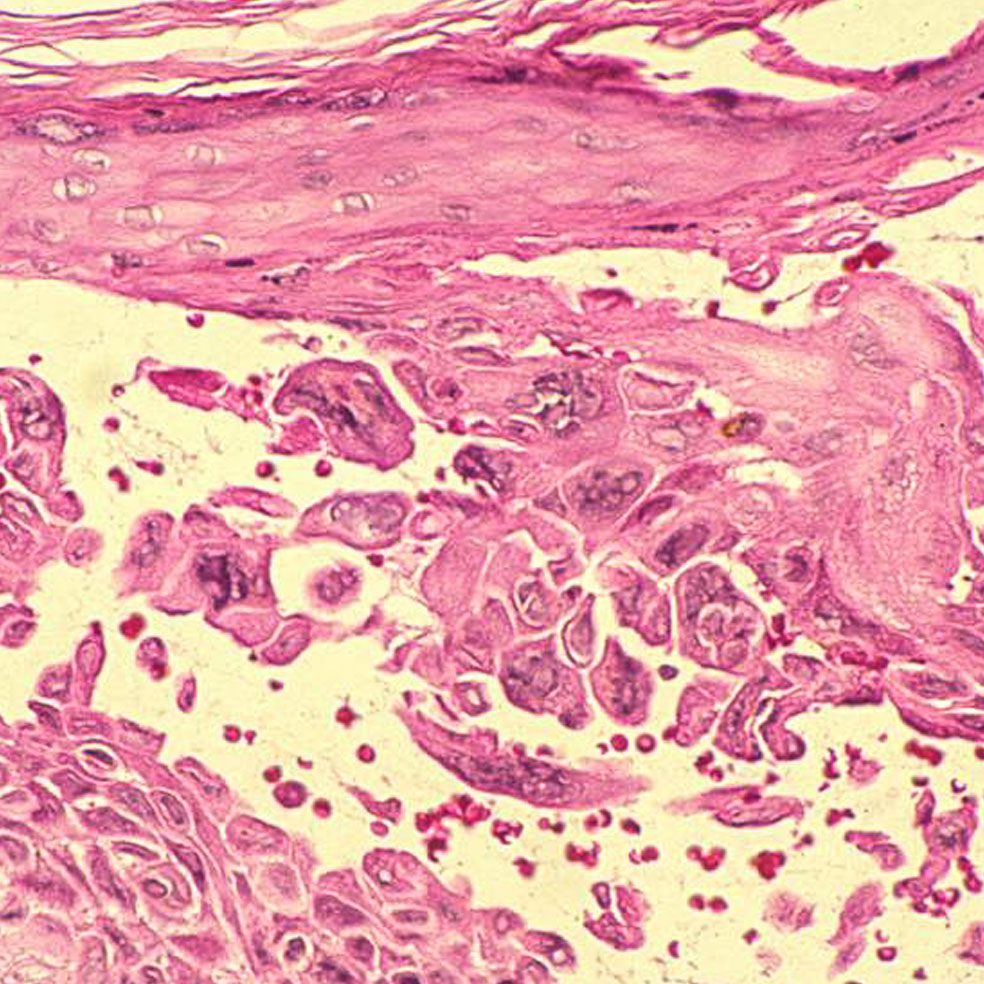

El origen se halla en tres tipos de hongos: Microsporum, Epidermophyton y Trichophyton, criaturas milenarias que invaden las capas superficiales de la piel, el pelo y las uñas. Es donde encuentran alimento y se reproducen. Por eso una vez ahí se multiplican, generando una erupción cutánea redondeada que se deshace en escamas y causa picor. Si no se trata a tiempo, puede provocar dolor, fiebre, caída del cabello e, incluso, alopecia en las zonas afectadas. Su capacidad de transmisión es muy elevada: basta tocar a una persona infectada u objetos contaminados como las máquinas en cuestión, peines, ropa, suelo de duchas, piscinas...

Trichophyton y Epidermophyton son dos géneros de hongos que se pegan a los pies en las duchas públicas, ocasionando una infección conocida como tiña podal o pie de atleta. Estos microorganismos proliferan en zonas cálidas y húmedas, por lo que se recomienda tener los pies limpios y secos, sobre todo entre los dedos.